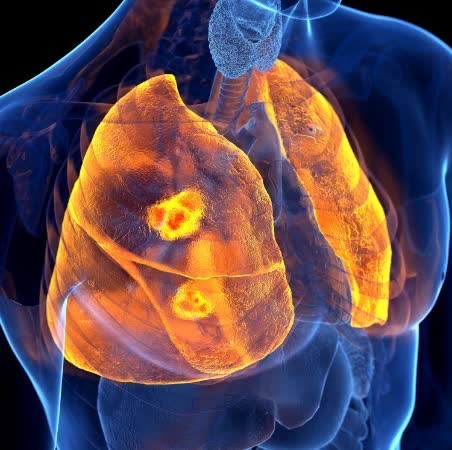

폐렴은 박테리아, 바이러스, 곰팡이, 기생충 등 여러가지 요인에 의해 발생할 수 있습니다. 세균성 폐렴이 가장 흔한 유형이며 일반적인 이유는 폐렴연쇄구균과 헤모필루스 인플루엔자입니다. 인플루엔자나 호흡기 세포융합 바이러스(RSV)로 인한 바이러스성 폐렴도 존재한다. 또한 진균성 폐렴은 특정 진균에 노출되어 발생할 수 있고, 마지막으로 드물기는 하지만 기생충성 폐렴도 있습니다.